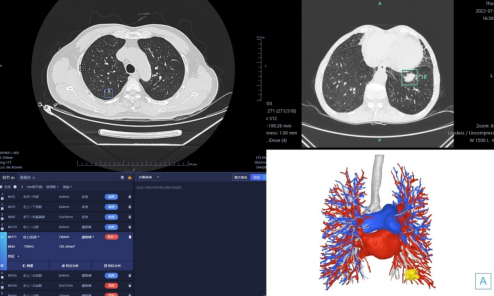

肺结节AI平台支持多种病灶的检出,并可以根据历史影像自动分析、对比结节变化及疗效评估,极大提升诊断效率。同时,肺结节三维重建系统可以对肺组织、血管、支气管、肺结节进行立体重现,明确结构空间立体关系,提供可视化图像,实现术前精准评估。